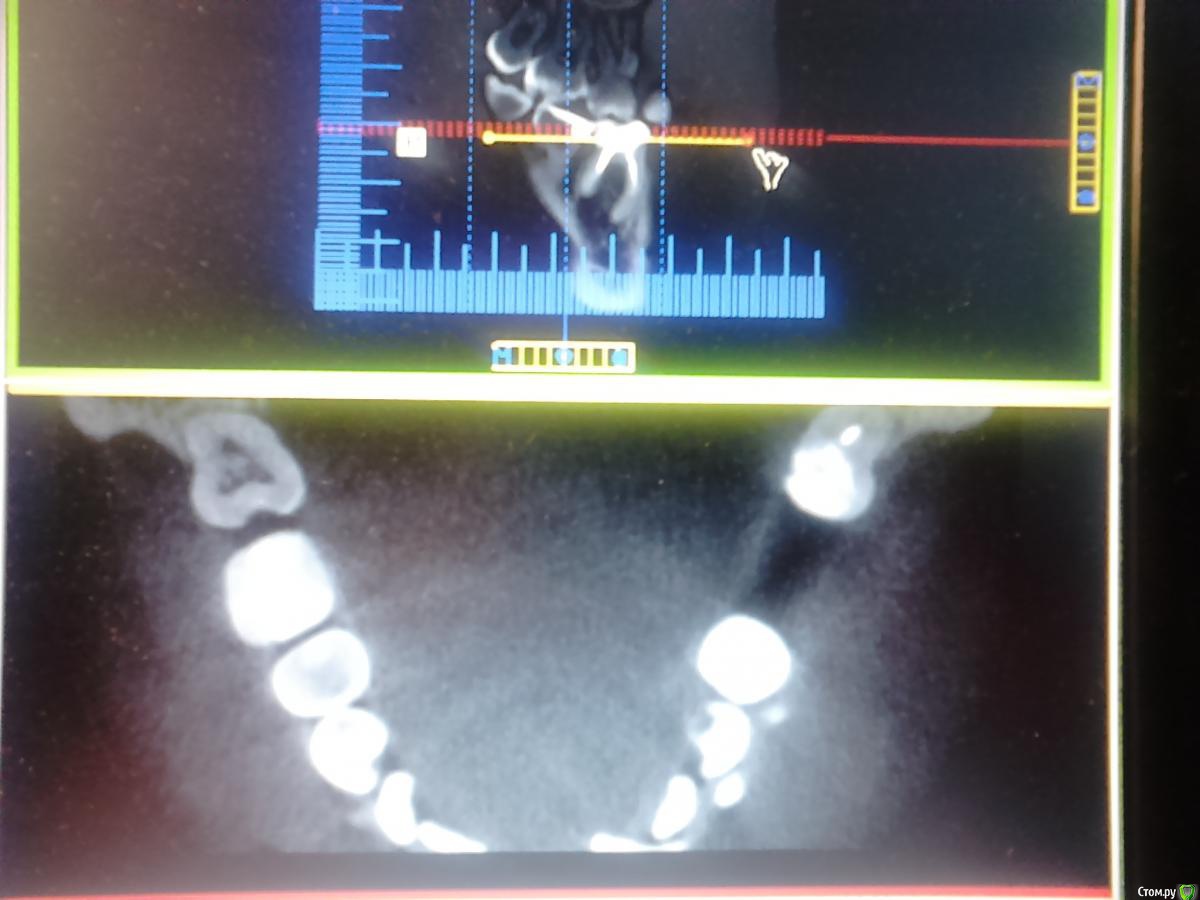

Фотина Опубликовано 12 декабря, 2016 Автор Поделиться Опубликовано 12 декабря, 2016 Появились) Ссылка на комментарий

Фотина Опубликовано 13 декабря, 2016 Автор Поделиться Опубликовано 13 декабря, 2016 https://yadi.sk/d/pxAOg2f-33PmD4 Это все КТ. https://yadi.sk/d/-B6PgdUP33Pm4R Только одна папка. КТ свежее, а панорамный снимок 2015 г. С 46 тоже надо что-то делать. Перепломбировка каналов (более 2 лет назад) не принесла положительных результатов: киста осталась ((( Ссылка на комментарий

IvanK Опубликовано 13 декабря, 2016 Поделиться Опубликовано 13 декабря, 2016 Вы говорите про 37 зуб, а показываете 4ый сегмент покажите весь панорамный снимок, скриншот кт интересующей зоны кт качать не у всех есть желание / возможность скачивать Ссылка на комментарий